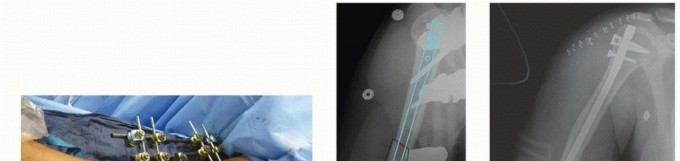

k DEFINITION A direct approach with the patient in a prone position to the posterior aspect of the tibial pla…